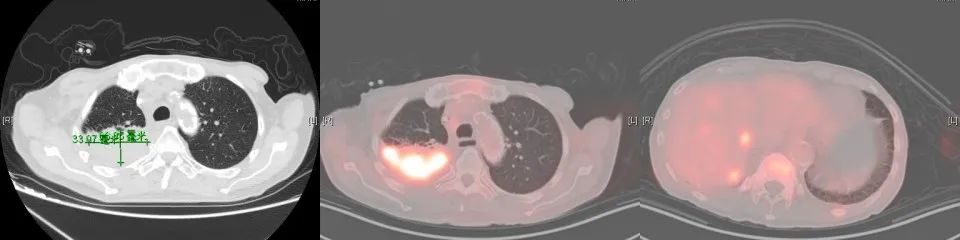

2017年7月行全身PET-CT提示右肺上叶高代谢病灶。2017年8月份行肺穿刺活检未能明确病理诊断。2017年10月份再次行全身PET-CT:右上肺结节增大,代谢增高,与家属商量后,外院予试用口服“吉非替尼”靶向治疗。

2018年1月复查胸部CT:右肺占位较前增大,余无明显特殊不适。外院再次行肺穿刺活检,病理:右肺组织见癌转移(符合膀胱癌肺转移)。2018年3月14-29日于我院行肺转移灶局部放疗。2018年5月15日-7月11日予标准方案化疗2周期。期间病情稳定。2018年10月复查,局部肺转移灶增大进展、且出现肺新转移灶,评估疗效PD,行NGS全基因检测,根据检测结果,即选用阿法替尼口服行靶向治疗。

CT变化: